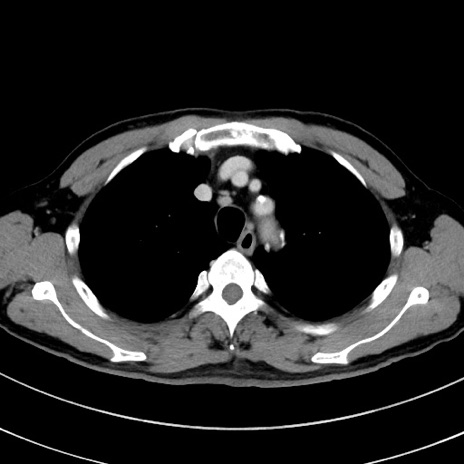

症例8(横断像)

【症例】 60歳代男性

【主訴】 黒色吐物

【現病歴】 4日前から嘔気自覚、2日前の朝食後にも嘔気あり、自分で手で嘔吐反射起こし嘔吐したところ血が混ざっていたため受診。

【既往歴】 5年前汎発性腹膜炎を伴う急性虫垂炎で手術、高血圧、前立腺肥大症、高脂血症

【身体所見】 腹部正中に手術癩痕あり 腹部平坦・軟圧痛なし膨満感あり

【データ】WBC 8400、CRP 4.54